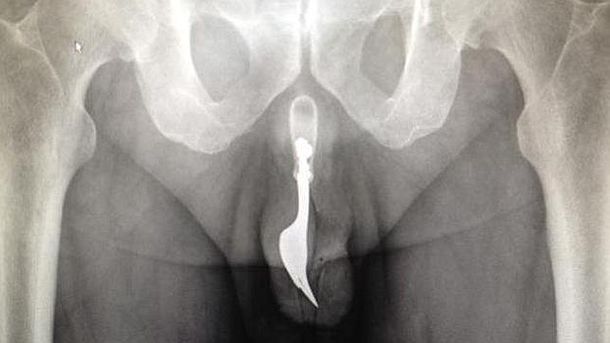

Un hombre de 70 años debió ser intervenido de urgencia para extraerle un tenedor que tenía en el interior de su pene, luego de que se le quedara incrustado al disfrutar sexualmente con el objeto.

El anciano, afectado por la vergüenza, tardó doce horas en ir a un hospital de Camberra, en Australia, donde tuvo que ser intervenido de urgencia.

Según informó ABC.es, los médicos debieron dormir con anestesia general al paciente para poder extraerle el tenedor de diez centímetros de longitud gracias a una laboriosa maniobra que requirió mucho lubricante y pinzas.